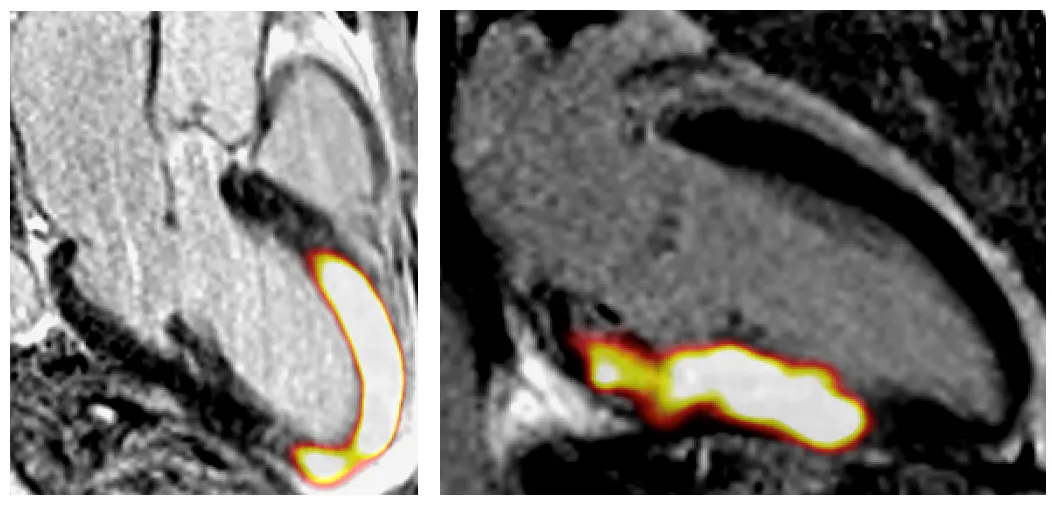

Two patients who had a recent heart attack scanned with the new imaging technique (FAPI-PET). Areas of active scarring are seen as bright yellow orange in the areas of the heart muscle damage by the heart attack. Areas of normal heart muscle appear black.

Researchers at the University of Edinburgh are to use pioneering imaging techniques to investigate scarring in the heart, which could pave the way for major advances to save and improve lives from heart disease.

Scarring of the heart tissue and muscle occurs in many different conditions including after heart attacks and in heart valve disease. When scar tissue builds up, it prevents the heart from beating efficiently, and is a major cause of heart failure – a debilitating condition for which there is no cure.

Up until now, scanning technology has only been able to detect scarring in patients once it has already formed, reducing treatment options.

Now, scientists have been given a grant of £671,000 from the British Heart Foundation (BHF) for a clinical study using state-of-the art scanning and imaging which, for the very first time, hopes to identify scarring in patients in the early stages as it is developing. This could mean patients being treated more effectively and ultimately, potentially before the effects of scarring are irreversible.